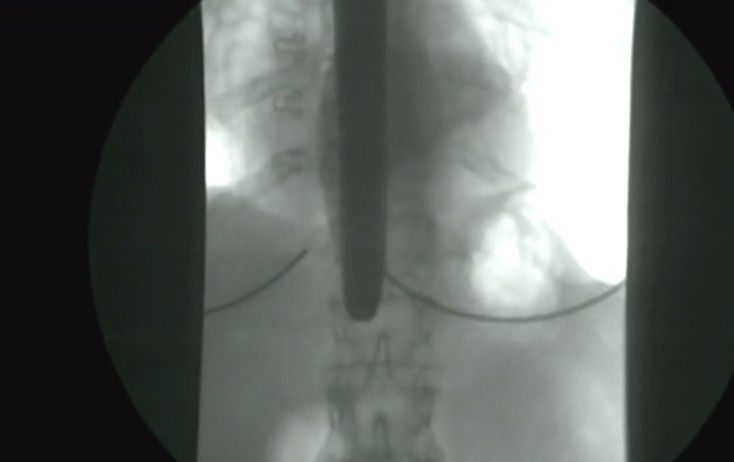

现场用X光扫描可以看到,一把长长的剪从女子喉咙里经过,一直到达胃部~